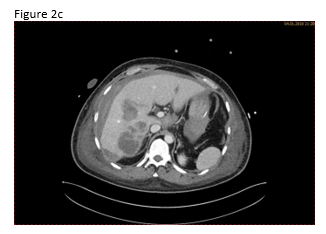

A 49 year old patient was admitted to the hospital for sepsis and shock of unknown origin. The patient presented with signs of sepsis and hemodynamic instability that justified an urgent approach including complex intensive care and intubation. Bedside ultrasound (US) found ascites and an abscess in the right liver lobe (9 cm) (Figure 1a). The patient was treated with broad-spectrum antibiotics and puncture and drainage of the abscess (Figures 1 a-c and 2 a-b). In addition, a biopsy was taken from the periphery of the lesion. A few days after the removal of the drainage the patient presented with a progressive elevation of liver enzymes. US revealed a cystic lesion measuring 30 mm that was proximal to the drained abscess (Figure 1a). Color Doppler Imaging (CDI) showed arterial flow inside the lesion, and contrast enhanced ultrasound (CEUS) showed early arterial enhancement and turbulent flow with a “to-and-fro” sign, suggestive of a pseudoaneurysm (Figure 1b). There was also a heterogeneously vascularized lesion with enhancing septae in the surrounding liver parenchyma (Figure 1c) . A few days later the patient presented with tachycardia and a drop of hemoglobin from 10 g/dl to 7 g/dl. US revealed spontaneous thrombosis of the pseudoaneurysm (Figure 1d) with intra - and perihepatic hemorrhage (Figure 1e).

Figure 2: Computed tomography (CT)showed abscess formation before drainage and perihepatic ascites (a). Twelve days after drainage removal a CT follow-up showed hyperenhancing intrahepatic lesion in proximity of the abscess, suggestive of a pseudoaneurysm (b). CT confirmed the spontaneous thrombosis of the pseudoaneurysm (c).